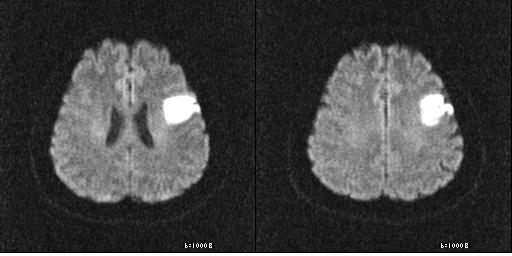

뇌경색 초기증상이 의심된다면 지금 바로 병원을 내방해 진단을 받고 적절한 치료를 손대는 것이 후유증을 감하는데 중요 해요. 시간이 관건이며, 뇌세포의 괴사, 증상 악화, 너무 늦으면 사망에 이를 수 있는 뇌혈관의 괴사를 피하기 위하여 증상이 나타난 뒤에 4시간 이내에 잘 맞은 약물, 시술 또는 수술을 신속히 실시해야 합니다. 치료로 즉시 하셔야 해요.